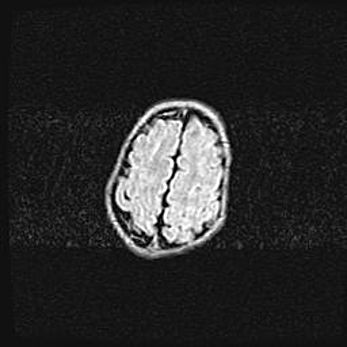

Неполная лизэнцефалия (пахигирия). Открытая гидроцефалия.

Возраст: 17 дней

Вес: 3110 г

Пол: мужской

Окружность головы: 33,5 см

Срок гестации: 35-36 недель

Лизэнцефалия—недоразвитие корковой пластинки и мозговых извилин в результате нарушения миграции нейронов коры. Поверхность мозговых полушарий гладкая. Микроскопически выявляется отсутствие нормальных слоев коры и скопление групп нейронов в подкорковом белом веществе.

Пахигирия—уменьшение числа вторичных извилин. В пораженном полушарии нервные клетки образуют толстый недифференцированный слой с неправильно расположенными нервными волокнами и группами гетеротопных клеток. Нервные клетки незрелые. Белое вещество истончено. При этом нередко аномально развит корково-спинномозговой путь.